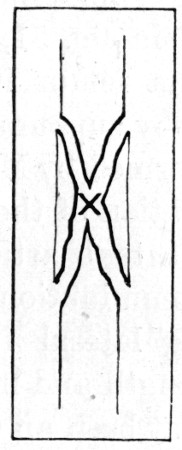

53a. Diagram of 'Butterfly' Type180

55a. Diagram of 'Butterfly' Type 200